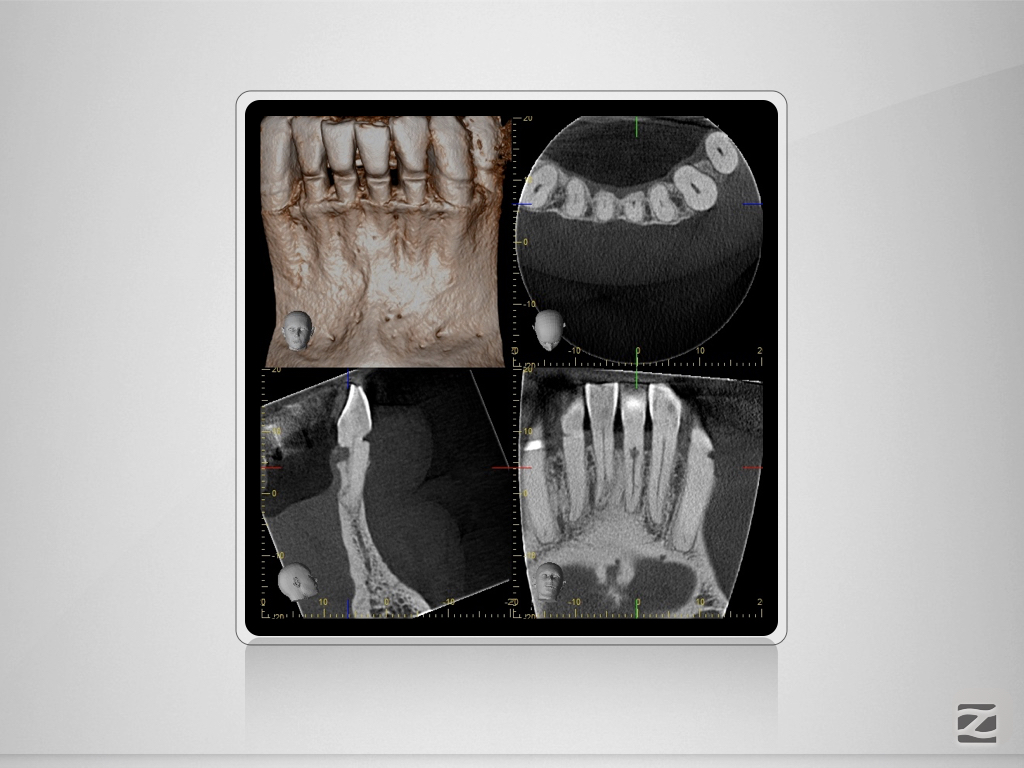

31D.013

Trauma, externe Resorption & Pulpotomie